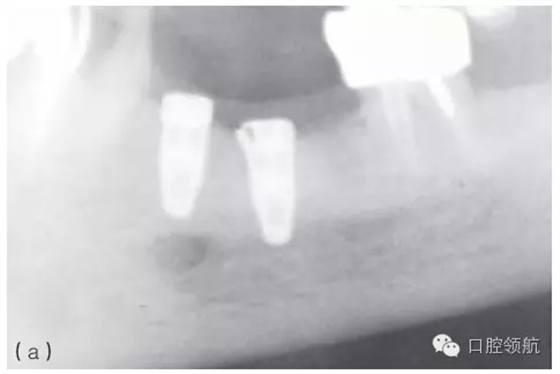

因種植體裝置界面的扭矩可能會(huì)使平臺(tái)連接出現(xiàn)潛在的變形,故應(yīng)注意使該扭矩最小化。Ⅳ類骨植入種植體時(shí)要優(yōu)先在骨上敲打擠壓而不是依靠種植體來擠壓骨洞。許多廠家會(huì)提醒不要超過手術(shù)操作時(shí)推薦的扭矩,以減小折斷的可能性(圖5.3a~c)。

圖5.3 (a)Ⅰ類骨中的種植體內(nèi)連接和界面破損的影像學(xué)表現(xiàn)。(b)取出種植體,發(fā)現(xiàn)沿著種植體平臺(tái)的損壞。(c)在重新放置的種植體上行聯(lián)冠修復(fù)完成2年后的影像學(xué)表現(xiàn)。